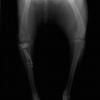

術後左後肢正面像

術前のTPAは左後肢33.1°右後肢26.8°でしたがTPLO実施により左後肢5.5°右後肢12°に矯正されました。